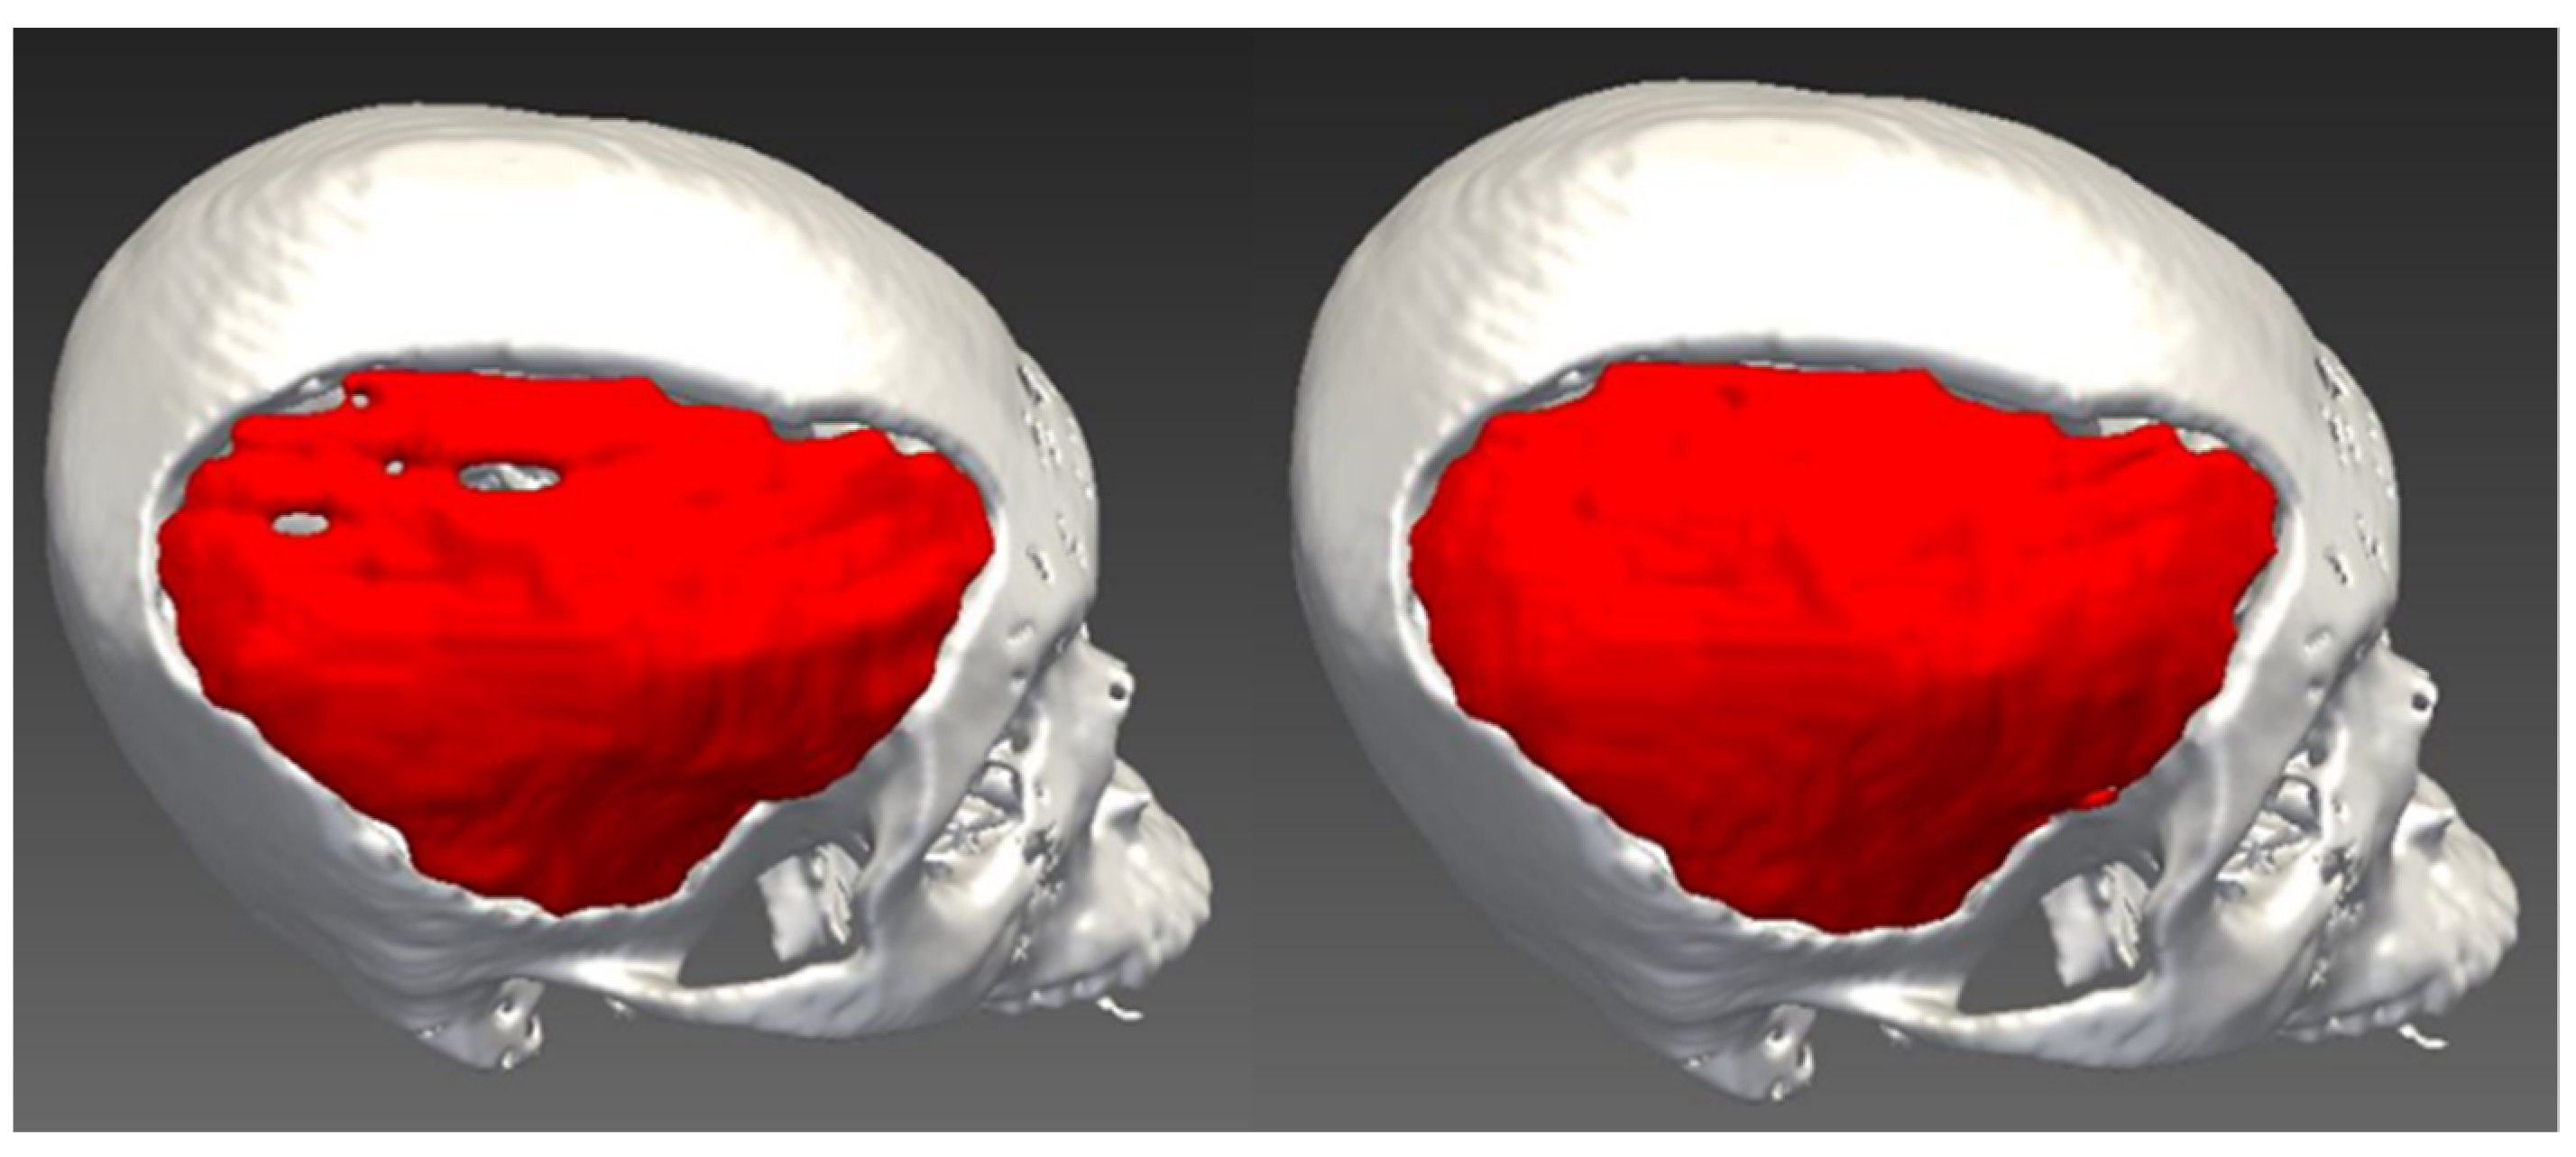

2.2. Design of Cranial Implants Using MITK Software

3. Results